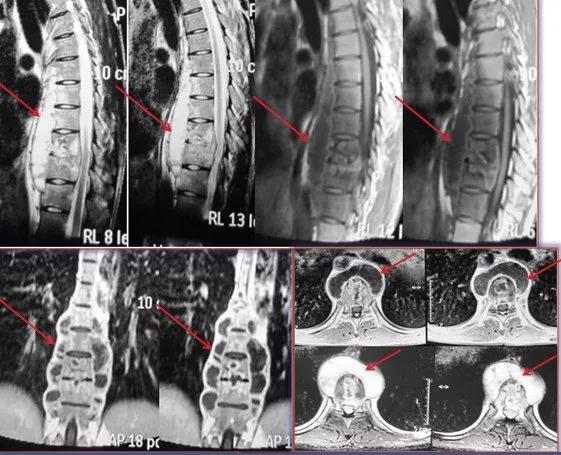

1、 这个患者是年轻男性,他因腰痛就诊。影像检查发现腰骶椎结核,从核磁看(红色箭头示)腰骶椎体有炎性表现,椎间隙狭窄,椎前有脓肿。

患者的腰痛不严重,可以下地活动,脓肿也不大。给予保守治疗,患者每个月门诊复查一次,通过影像及化验检查定期观察治疗效果及药物副作用,根据结果动态调整治疗药物,用药一年后,患者疼痛缓解,从核磁看(红色箭病灶吸收,达到治愈。